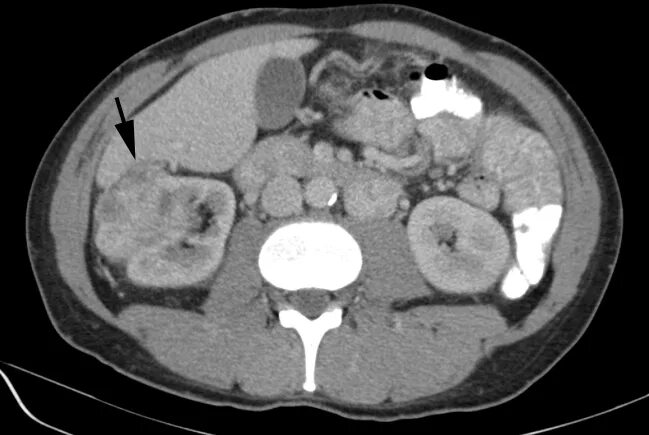

Туберкулезный склероз